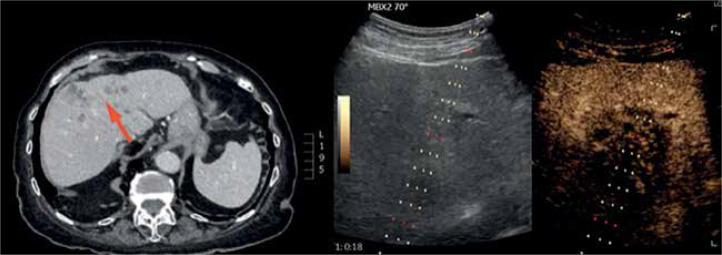

本研究的目的是确定对比增强超声(CEUS)在肝活检中的有用性。腹腔显像技术的普及,尤其是超声(USG),导致局灶性肝病变(FLL)的检出率增加。如果其他成像方式(磁共振成像[MRI]或计算机断层扫描[CT])的结果不确定,则应考虑经皮肝活检。考虑到在肝活检中使用MRI和CT的局限性,该程序主要是通过超声进行的。它经济、安全、快捷。无论何时,如果无法在b层显示病变(这是安全有效的活检所必需的条件),建议使用先进的超声技术-超声造影或融合成像。融合成像的局限性包括数据处理时间长,难以实现图像的最佳重叠。相反,超声造影增强病变的可视化,但没有上述限制-它是快速的,不需要额外的处理。此外,考虑到超声造影在肝局灶性病变的可视化和坏死区域的分化方面的潜力,以及检测神经内分泌肿瘤或其转移的能力,我们坚信超声造影辅助下的活检程序-特别是核心针活检-是当代诊断的有力工具。在本文中,我们想分享我们中心的经验,并回顾在超声造影指导下进行肝活检的现有文献。

The aim of this study is to determine the usefulness of contrast-enhanced ultrasound (CEUS) in liver biopsy. The popularisation of imaging techniques that visualise the abdominal cavity, especially ultrasonography (USG), has resulted in an increase in the detection of focal liver lesions (FLL). If the results of other imaging modalities (magnetic resonance imaging [MRI] or computed tomography [CT]) are inconclusive, percutaneous liver biopsy should be considered. Taking into account the limitations of using MRI and CT in liver biopsy, this procedure is mostly performed with ultrasound. It is economical, safe, and swift. Whenever it is impossible to visualise lesions in B-mode (a condition necessary for a safe and effective biopsy), it is advisable to use advanced ultrasound techniques - CEUS or fusion imaging. Limitations of fusion imaging include prolonged time of data processing and difficulties in achieving optimal overlap of images. Conversely, CEUS enhances lesion visualisation but is devoid of the mentioned limitations - it is rapid and requires no additional processing. Furthermore, considering the potential of CEUS in the visualisation of focal liver lesions and differentiation of necrotic areas, accompanied by the ability to detect neuroendocrine tumours or its metastasis, we strongly believe that biopsy procedures - especially core needle biopsies - with CEUS assistance are potent tools in contemporary diagnostics. In this paper we want to share the experience of our centre and review the available literature on performing liver biopsies under CEUS guidance.